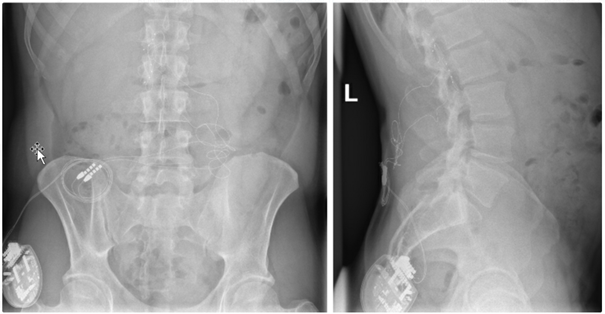

Bei der Rückenmarkstimulation wird in der Wirbelsäule eine Elektrode platziert. Über diese werden elektrische Impulse an das Rückenmark abgegeben. Die Elektrode ist mit einem Impulsgeber (vergleichbar mit einem Herzschrittmacher) verbunden. Das operative Verfahren gliedert sich in zwei Abschnitte: Im ersten Eingriff erfolgt, unter örtlicher Betäubung und Röntgenkontrolle, die Platzierung der Elektrode im Rückenmarkskanal. Im Anschluss erfolgt eine Testphase. Ziel ist es, die Abdeckung des Schmerzareals durch die Stimulation und die daraus resultierende Schmerzreduktion zu testen. Bei zufriedenstellendem Ergebnis wird in einem zweiten Eingriff der Impulsgeber unter die Haut implantiert.

Die über die Elektrode abgegebenen Impulse bewirken im Bereich des Rückenmarks eine Unterbrechung/Verminderung der Schmerzleitung der Nerven. Hierbei ist es notwendig, bei jedem Patienten individuell die notwendigen Stimulationsparameter festzulegen. Die schmerzreduzierende Wirkung der Neurostimulation kann in einem zweiten Schritt die Verringerung der Schmerzmedikation nach sich ziehen.

Röntgenbild zur Rückenmarkstimulation